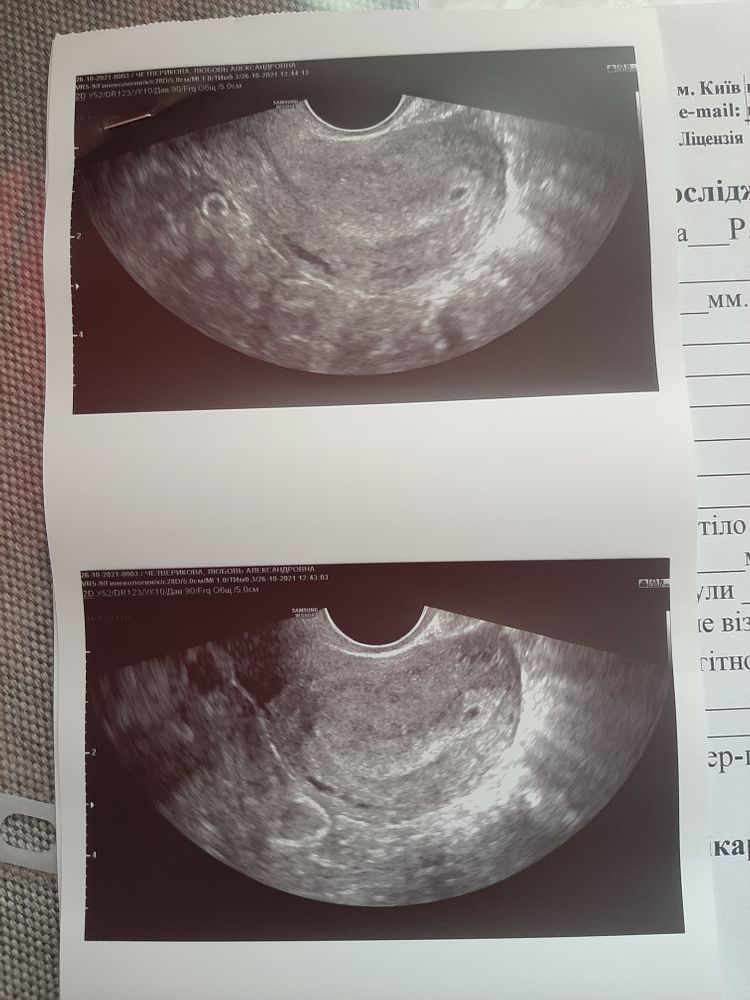

Вопросы про УЗИ, обследования и анализы: что, где, как, когда?Срок совсем маленький. Долго искали и сказали, что нашли яйцо прикрепленное высоко в матке, но в заключении ничего об этом не сказано. Только про жёлтое тело в правом яичнике 17.4 мм.

Так написано, узи признаки маточной беременности малого срока, контроль через месяц.

Олеся Гонцова, да, но почему ничего не пишут про плодное яйцо. Его получается нет? Или это оно на фото?